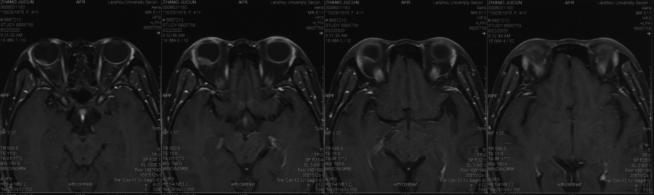

• Orbital MRI (Right Eye):A mound-shaped abnormal signal with mild enhancement was observed on the posterior upper and lower walls of the right eyeball, suggestive of melanoma.

• Vision and Intraocular Pressure: Monitored before, during, and after treatment (Table 1). Post-treatment MRI showed slight tumor enlargement with no light perception. One-month follow-up MRI revealed stable disease (SD) (Figure 4).

Figure 4: Abnormal mound-shaped signal on the posterior upper and lower walls of the right eyeball, showing mild enhancement. Melanoma cannot be ruled out. A nodule is observed on the posterolateral wall of the right eyeball, exhibiting short T1 and T2 signals, with high signal on DWI

Evaluation of Visual Acuity and Intraocular Pressure: Visual acuity and intraocular pressure were assessed before, during, and after treatment. Post-treatment MRI revealed a slight increase in tumor size, with no light perception. One month after treatment, MRI showed no significant change in tumor size compared to pre-treatment, and the efficacy was evaluated as stable disease (SD).